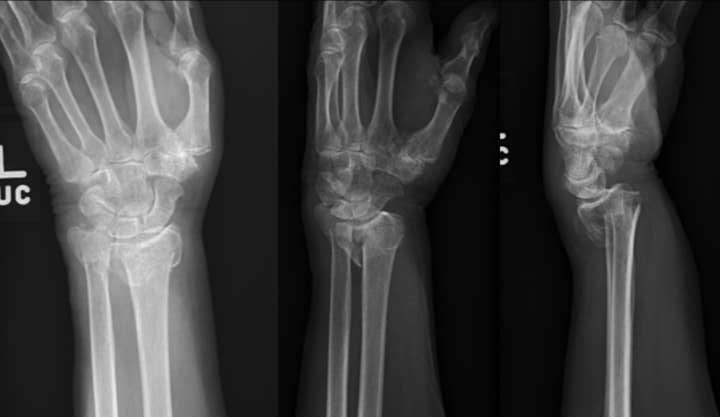

Anteroposterior, lateral, and oblique preoperative images of distal radius and ulna fractures